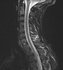

В результате седьмой шейный позвонков сильно "стерся", а его остистый отросток треснул, не выдержав нагрузок. Как подчеркивают медики, это первый в мире стрессовый перелом из-за виртуальной реальности, обычно от таких травм страдают спортсмены, военнослужащие и шахтеры. Врачи обследовали пациента при помощи магнитно-резонансной томографии и исключили дефект мягких тканей, после чего начали лечение с обезболивающими препаратами. Спустя 6 недель ношения бандажа, немец восстановился без осложнений.